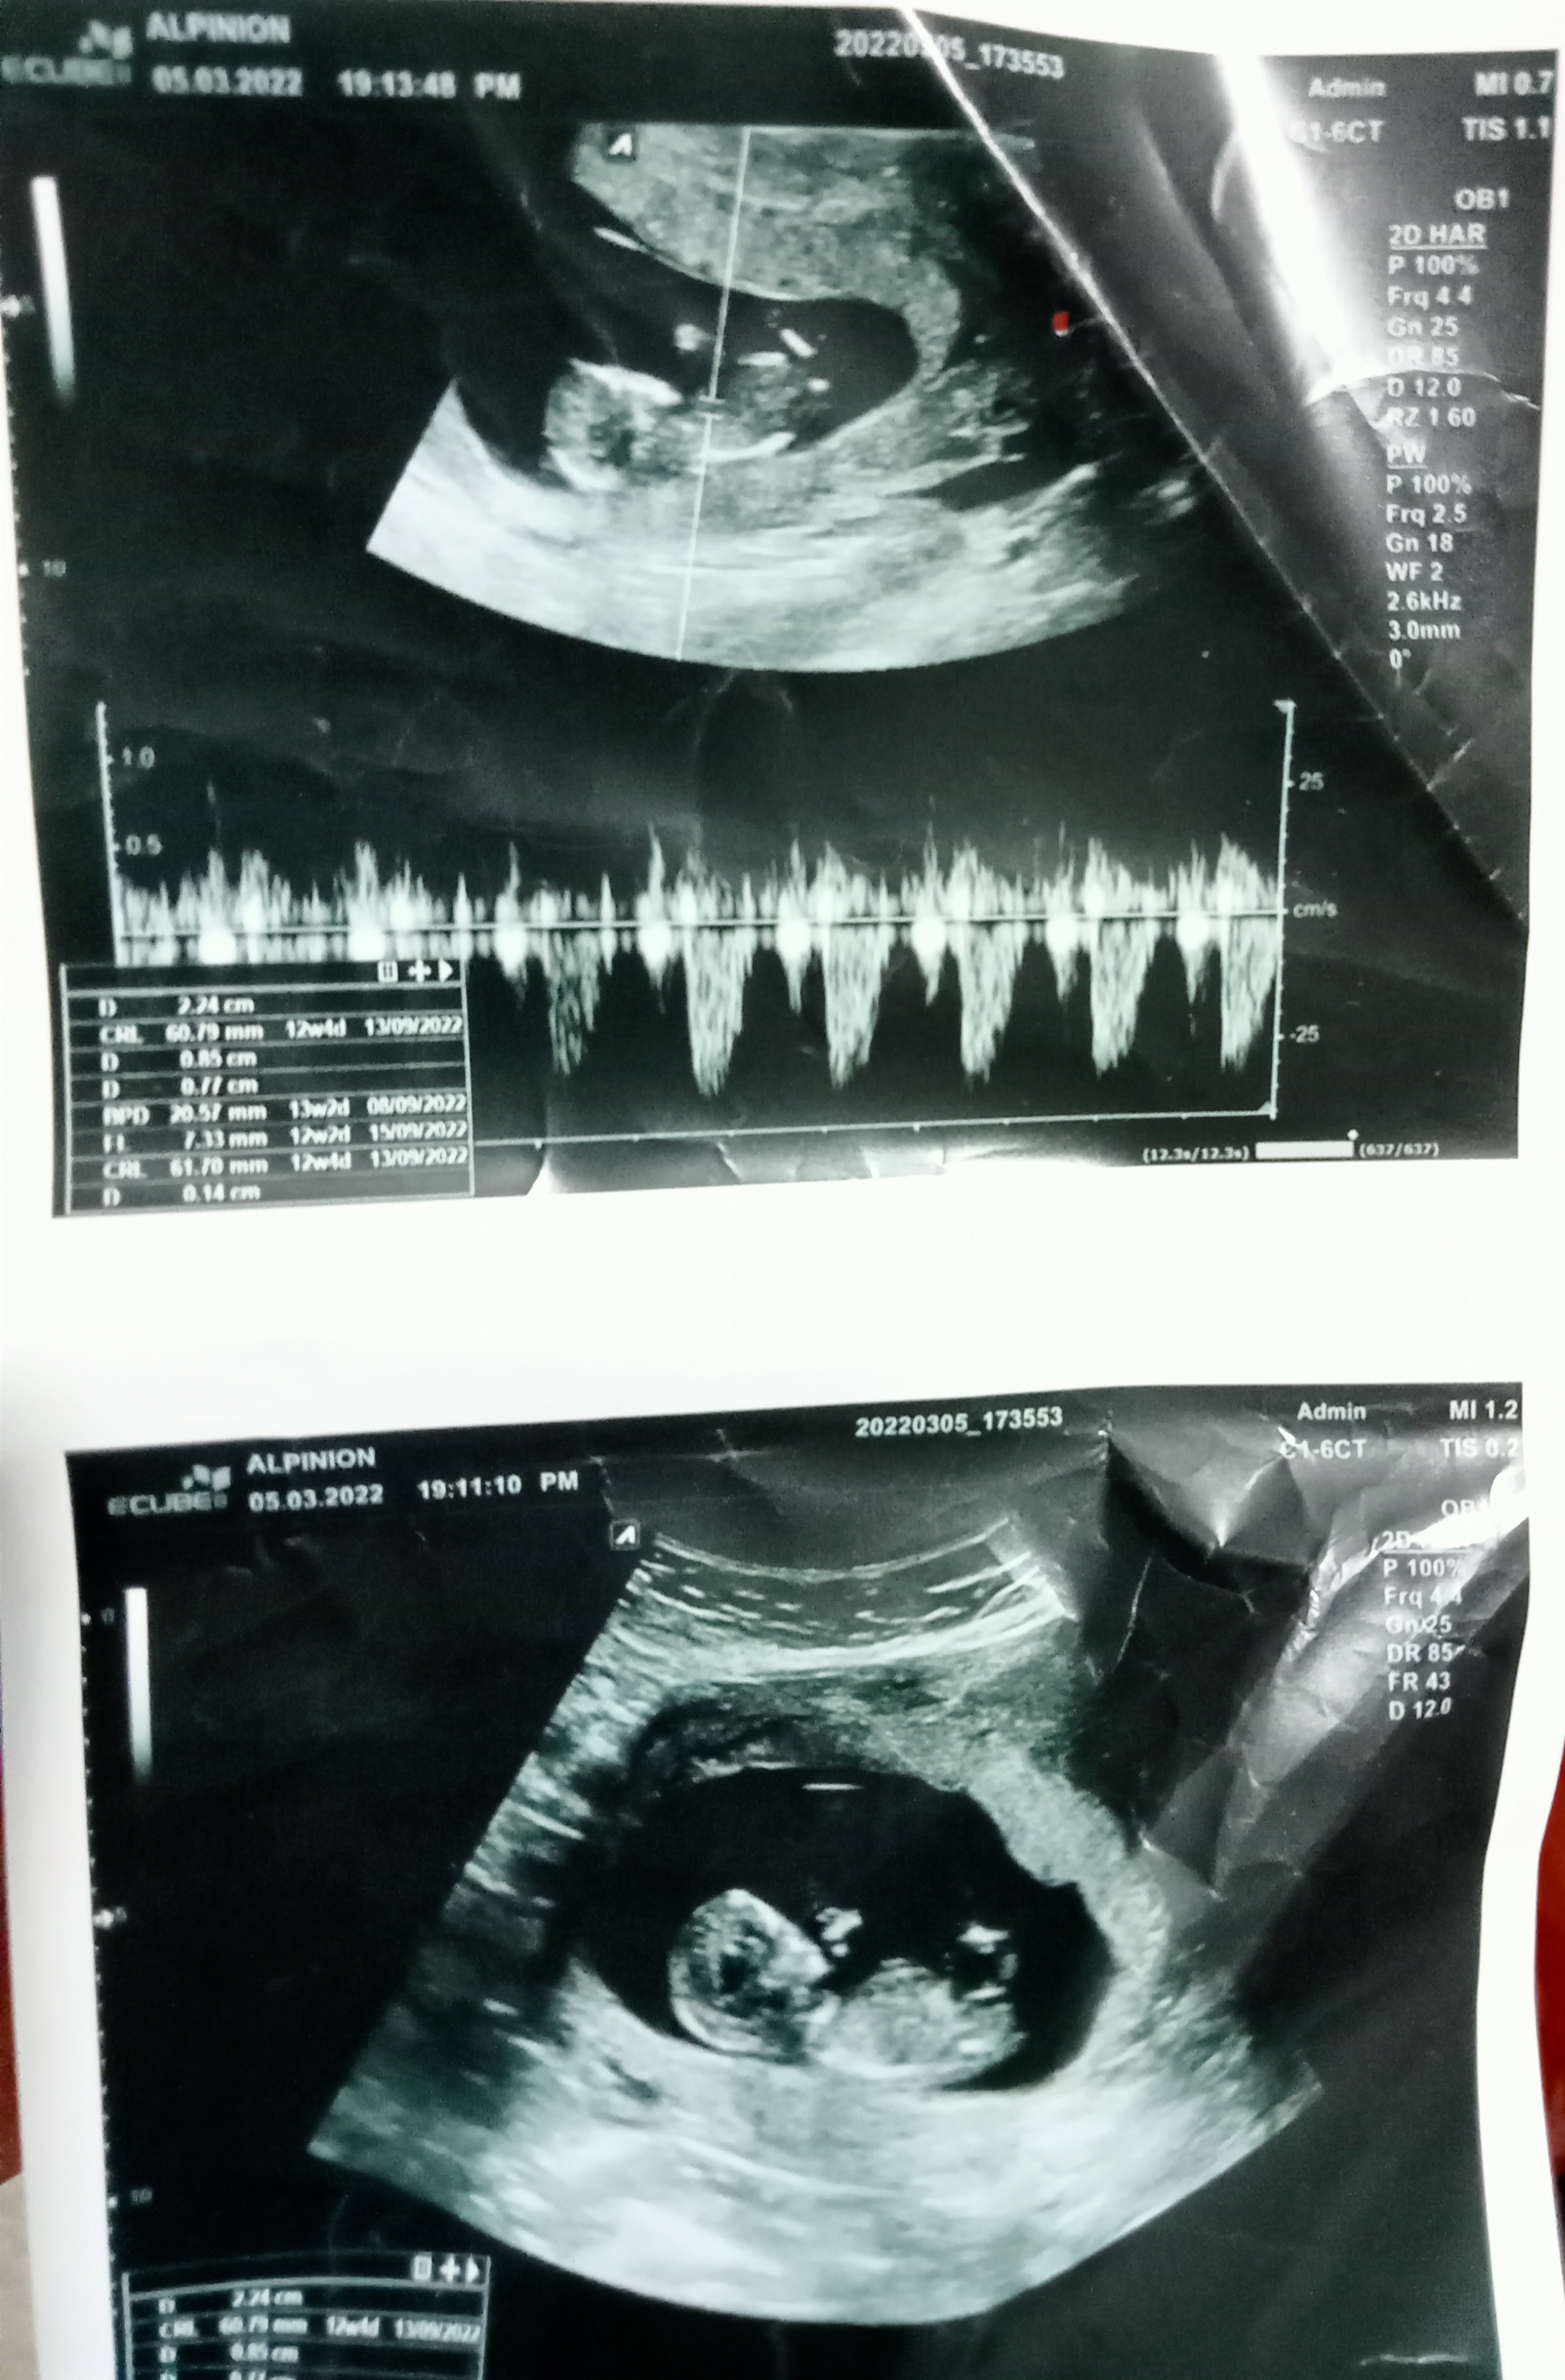

Rüzgar gülü canım baktım inceledim ama çok flu çekilmiş gorseller daha net olanı yok mu ya da daha net çekebilsen daha iyi yorumlayabiliriz

merhaba banada bakabilir misiniz acaba

Selamlar Sevgili Nermin, Resmi baya inceledim ama görmemiz gereken genital tüberkülül görünmüyor dolayısı ile bir cinsiyet tahmini malesef yapamıyorum. Başka resim var ise yükleyin onlara da bakalım olur mu ?